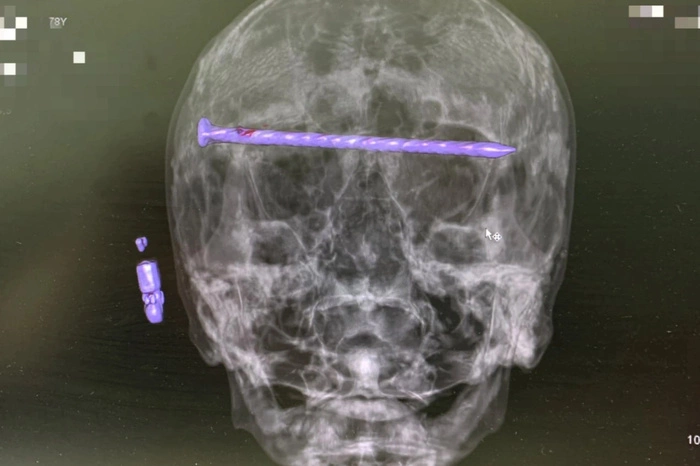

В Нижнем Тагиле врачи вытащили из головы 78-летнего пациента 15-сантиметровый гвоздь.

Фото: Минздрав Свердловской области

Мужчина поступил в приёмный покой горбольницы № 1 в тяжёлом состоянии. На КТ медики обнаружили в костях черепа гвоздь, прошедший через обе глазницы от правого до левого виска. Ситуация осложнялась повреждением оболочки мозга и сдавлением глазных яблок.

Экстренную операцию провела бригада во главе с заведующим нейрохирургическим отделением Дмитрием Неволиным. Пациенту удалось сохранить жизнь и зрение.

— Прооперированный мужчина под наблюдением бригады врачей восстанавливается. Для профилактики осложнений он проходит антибактериальную терапию и готовится к выписке, — отметили в Минздраве региона.